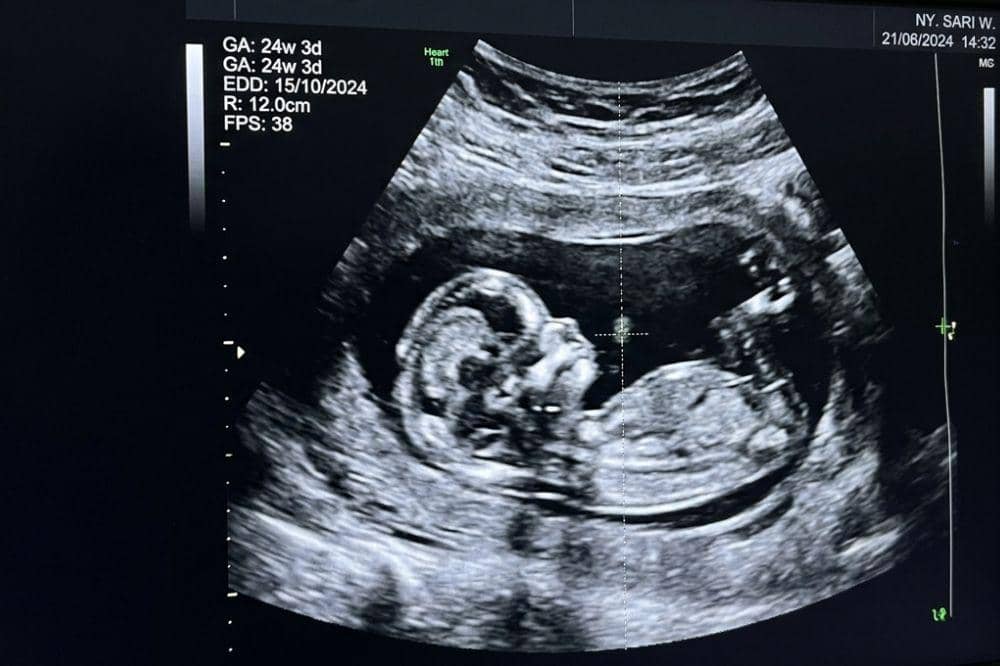

10. Bayi sudah bisa berekspresi saat berada di dalam tubuh mama

Apakah Mama membayangkan seperti apa ekspresi pertama bayi saat lahir nanti? Ternyata, jauh sebelum itu, bayi sudah mulai menunjukkan berbagai ekspresi wajah di dalam rahim. Hasil USG bahkan memperlihatkan bayi bisa melakukan gerakan seperti menangis, tersenyum, hingga menggerakkan wajahnya.

Hal ini bukan berarti bayi sedang sedih, melainkan bagian dari proses perkembangan otot dan saraf wajah. Kemampuan ini nantinya akan menjadi dasar penting bagi bayi untuk berkomunikasi setelah lahir, terutama melalui tangisan di minggu-minggu awal kehidupannya.